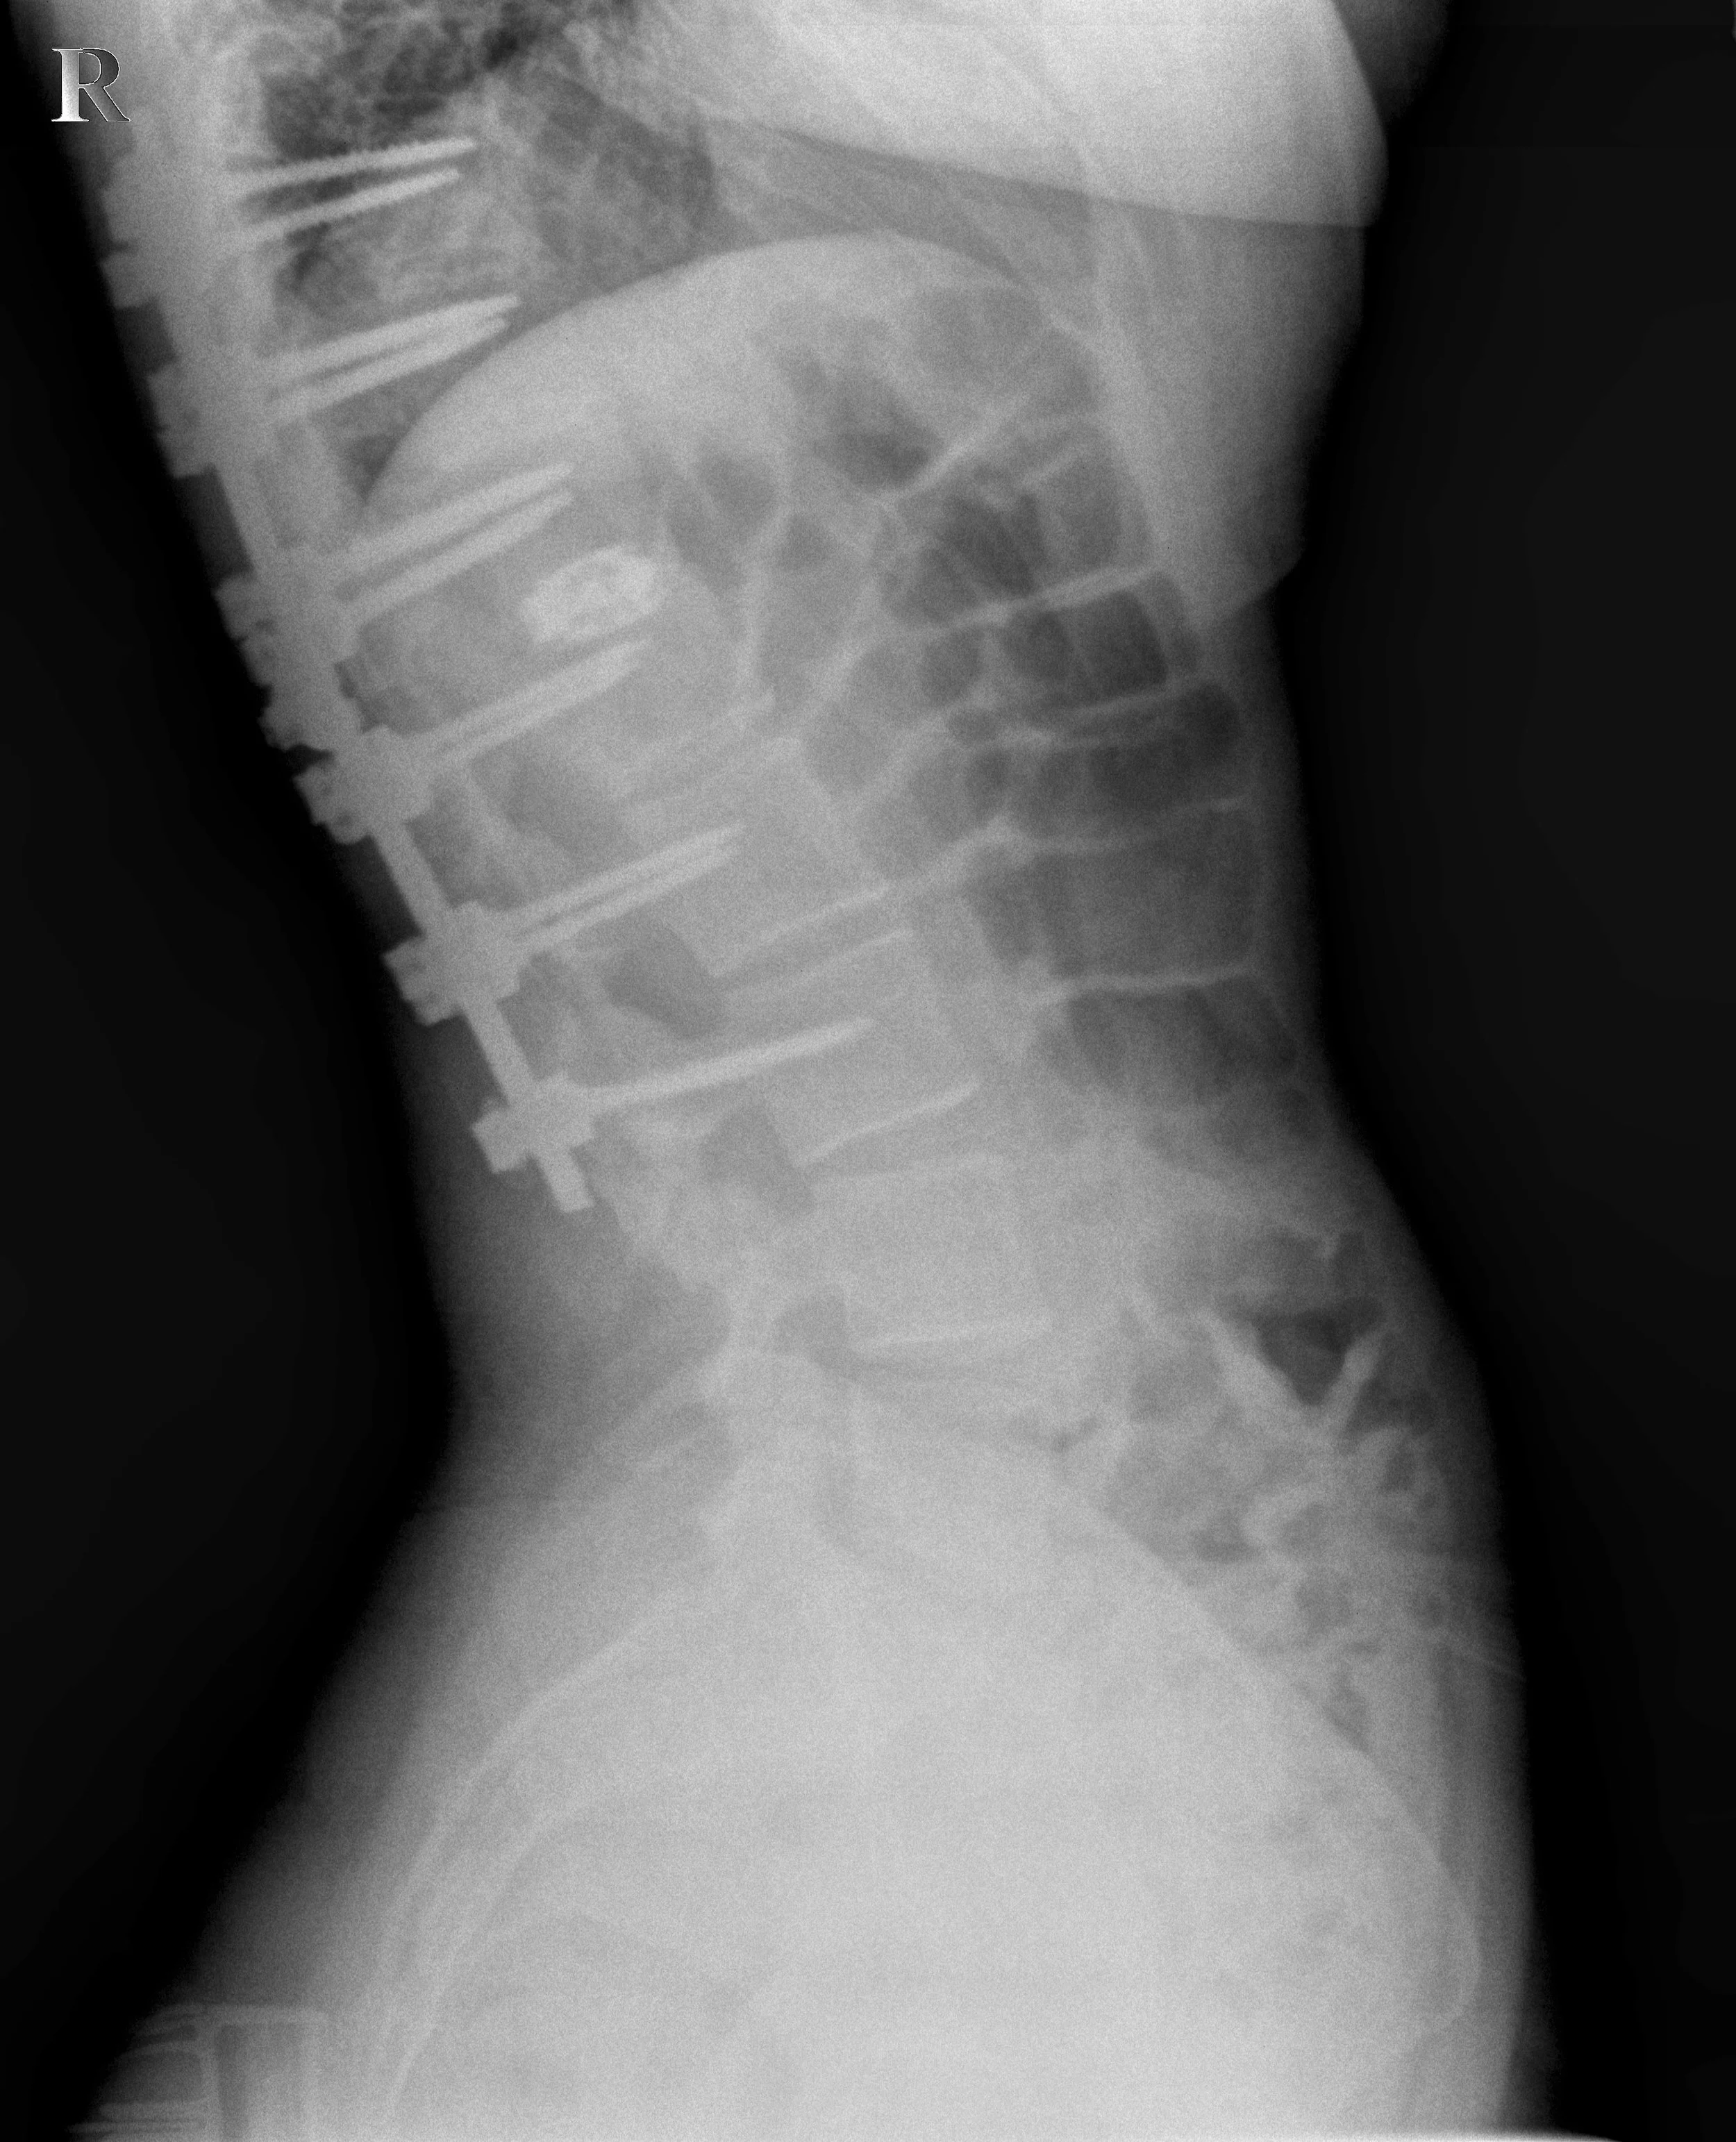

Chiropractic Care & Spinal Fusions: A Patient Case

Read all about spinal fusion, what it means for your spine, and how chiropractic care can help — featuring a real patient case from our office!